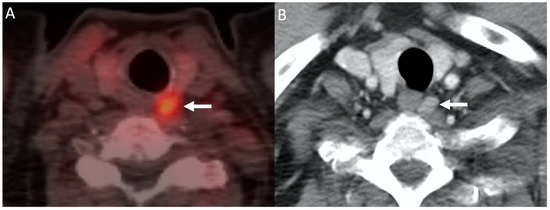

- Parvinian, A.; Martin-Macintosh, E.L.; Goenka, A.H.; Durski, J.M.; Mullan, B.P.; Kemp, B.J.; Johnson, G.B. 11C-Choline PET/CT for Detection and Localization of Parathyroid Adenomas. Am. J. Roentgenol. 2018, 210, 418–422. [Google Scholar] [CrossRef] [PubMed]

- Liu, Y.; Dang, Y.; Huo, L.; Hu, Y.; Wang, O.; Liu, H.; Chang, X.; Liu, Y.; Xing, X.; Li, F.; et al. Preoperative Localization of Adenomas in Primary Hyperparathyroidism: The Value of 11C-Choline PET/CT in Patients with Negative or Discordant Findings on Ultrasonography and 99mTc-Sestamibi SPECT/CT. J. Nucl. Med. 2019, 61, 584–589. [Google Scholar] [CrossRef]

- Kluijfhout, W.P.; Vorselaars, W.M.; Vriens, M.R.; Rinkes, I.H.B.; Valk, G.D.; De Keizer, B. Enabling minimal invasive parathyroidectomy for patients with primary hyperparathyroidism using Tc-99m-sestamibi SPECT–CT, ultrasound and first results of 18F-fluorocholine PET–CT. Eur. J. Radiol. 2015, 84, 1745–1751. [Google Scholar] [CrossRef]

- Fischli, S.; Suter-Widmer, I.; Nguyen, B.T.; Muller, W.; Metzger, J.; Strobel, K.; Grünig, H.; Henzen, C. The Significance of 18F-Fluorocholine-PET/CT as Localizing Imaging Technique in Patients with Primary Hyperparathyroidism and Negative Conventional Imaging. Front. Endocrinol. 2018, 8, 380. [Google Scholar] [CrossRef]

- Thanseer, N.; Bhadada, S.K.; Sood, A.; Mittal, B.R.; Behera, A.; Gorla, A.K.R.; Kalathoorakathu, R.R.; Singh, P.; Dahiya, D.; Saikia, U.N.; et al. Comparative Effectiveness of Ultrasonography, 99mTc-Sestamibi, and 18F-Fluorocholine PET/CT in Detecting Parathyroid Adenomas in Patients With Primary Hyperparathyroidism. Clin. Nucl. Med. 2017, 42, e491–e497. [Google Scholar] [CrossRef] [PubMed]

- Huber, G.F.; Hüllner, M.; Schmid, C.; Brunner, A.; Sah, B.; Vetter, D.; Kaufmann, P.A.; Von Schulthess, G.K. Benefit of 18F-fluorocholine PET imaging in parathyroid surgery. Eur. Radiol. 2018, 28, 2700–2707. [Google Scholar] [CrossRef]